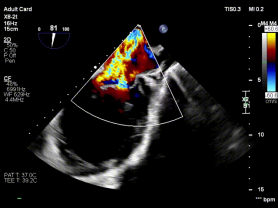

【图片6:术前超声图】

病例2为复杂功能性二尖瓣反流(FMR),术前影像提示前后瓣叶对合不良,存在明显间隙(GAP),反流程度达极重度。该类病例因瓣叶牵拉明显、张力大,是TEER技术中的典型难点。

针对该病例特点,团队制定个体化诊疗策略,在穿刺位置、器械路径及夹持方式上进行精细设计。术中,团队优化房间隔穿刺高度与位置,匹配GAP结构特点;反复调整导向系统,确保器械垂直对准反流中心;通过多平面及三维TEE确认最佳夹持窗口;采用分步夹持策略,提高瓣叶抓取成功率,确保手术过程平稳。